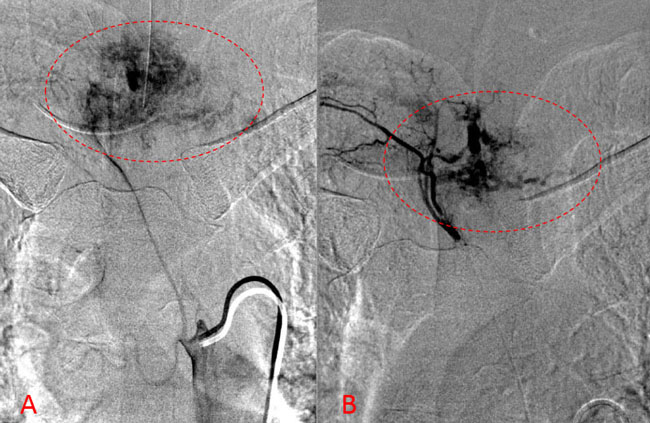

Figure 1. A) Sagittal T2 MRI demonstrates aggressive hyperintense T3 hemangioma involving the body and posterior elements compressing the thoracic spinal cord (arrows)

Figure 1. B and C) Axial MRI images of T3 demonstrates extensive infiltrative lesion with extradural compression of the thoracic spinal cord. (Dashed lines in A) tumor infiltration; Dashed lines and Arrows in B) cord compression.

He presented to the emergency room with one-week history of thoracic pain in addition to bilateral lower extremity weakness and paraparesis. MRI imaging with contrast showed a diffuse abnormal signal within the vertebral body of T3 and the posterior elements with lobulated soft tissue lesion extension into both paraspinal areas (Figure 1. A, B, C).